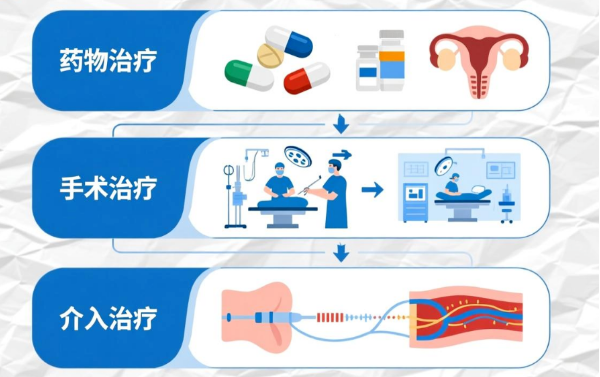

面对子宫腺肌症,临床上有多种管理方式,各有其侧重点。

1、药物治疗(如激素类药物)常用于缓解症状、控制病情发展,但部分患者可能面临停药后症状反复,或需要考虑药物的长期影响。

2、手术治疗中的子宫切除术,虽可解决病症,但也意味着永久失去子宫。对于有生育需求或希望保留器官的女性而言,这常是一个艰难的决定。而病灶切除术,则对病灶范围有一定要求。

3、在这样的背景下,介入治疗以其“微创”与“保器官”的特点,成为一种可供考虑的选择。